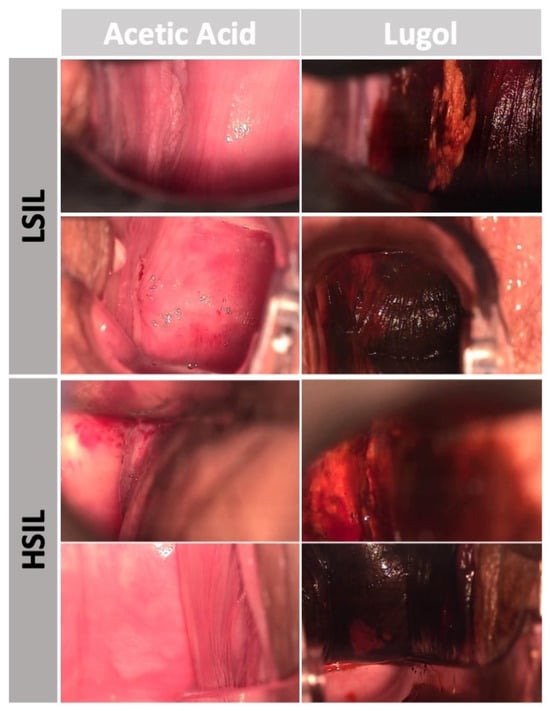

Figure 1. Examples of LSIL and HSIL frames (with acetic acid or lugol staining) during assessment of the vagina during colposcopy.

A total of 71 vaginoscopy procedures were ultimately included and a dataset of 57,250 frames was assessed. From the collected frames, 25,455 were classified as HSILs, and the remaining 31,795 frames were categorized as LSILs. The biopsy histopathology report from the vaginoscopy evaluation of the observed lesion was consistently referenced to classify each corresponding frame as either an HSIL or LSIL (Figure 1).